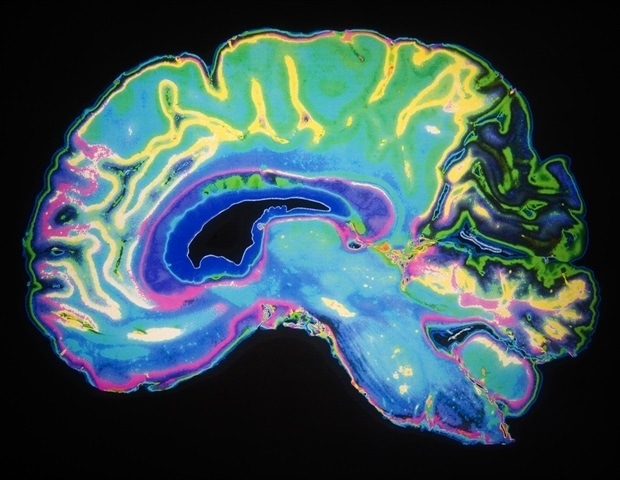

Исследователи из Питтсбургского университета и детской больницы UPMC в Питтсбурге обнаружили новый многообещающий биомаркер «осложненной» детской черепно-мозговой травмы легкой и тяжелой степени, или ЧМТ. В отличие от сотрясения мозга, которое обычно проходит в течение нескольких недель, осложненная ЧМТ требует, как минимум, пребывания в больнице на ночь, что сигнализирует о более серьезной травме.

Основываясь на многолетнем наследии инноваций в Центре реанимационных исследований Питта Сафара, новое исследование дополняет растущие знания о биомаркерах ЧМТ у детей. В своем исследовании команда сосредоточилась на модификациях нейротрофического фактора головного мозга. (BDNF) из-за его роли в нейропластичности, то есть способности мозга к реорганизации и заживлению после травмы. Предыдущие исследования связывали уровни BDNF с результатами восстановления после ЧМТ у взрослых, но до сих пор ни одна группа не изучала его эпигенетические модификации у детей.

Сосредоточив внимание на одном из наиболее широко изученных типов эпигенетических модификаций - метилировании ДНК, исследователи смогли проанализировать, являются ли уровни метилирования BDNF. могут служить динамическими биомаркерами, которые отражают как биологические, так и психосоциальные факторы, влияющие на выздоровление, предлагая уникальную молекулярную линзу для детской ЧМТ.

Ученые проанализировали образцы крови детей, не имевших в анамнезе ЧМТ или неврологических заболеваний, собранные в течение нескольких часов, дней и месяцев после того, как дети были госпитализированы в детский сад UPMC с осложненной легкой, средней или тяжелой ЧМТ. Их анализ показал, что в период острого восстановления дети с ЧМТ имели другой эпигенетический профиль по сравнению с детьми с ортопедической травмой. травмы: образцы крови детей с ЧМТ имели значительно меньшее метилирование ДНК BDNF, при этом уровни метилирования стабилизировались и достигали уровня контрольной группы через 12 месяцев после травмы.